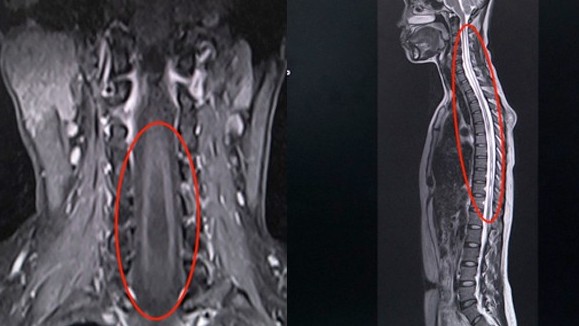

Tưởng đau cổ vai gáy, đi khám phát hiện căn bệnh có thể gây liệt tay

Thời sự xã hội -  14/04/2021

Chị H., 41 tuổi là nhân viên văn phòng ở Hà Nội. Hai tháng nay, chị thường xuyên đau vùng cổ gáy, nhức vai phải. Ban đầu chị nghĩ do công việc ngồi n...